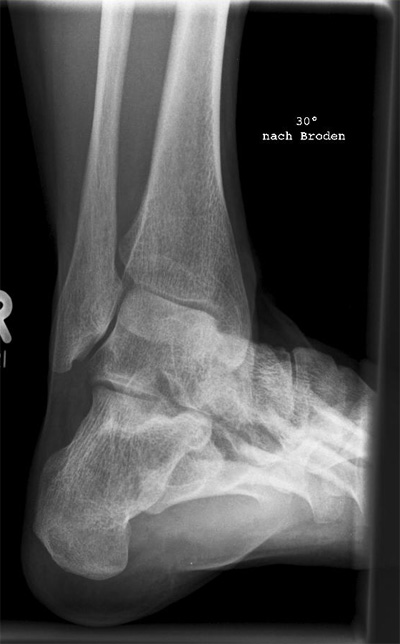

Broden I Außenrotation

Technik

• FDA: 1,05 m

• Ausgangsformat: 18/24

• Röhrenkippung

• Übertischaufnahme

Lagerung

sitzend/ liegend auf Tisch

Bein ausgestreckt und 45° nach außen (lateral) gegen ein 45° Keil drehen lassen

Fuß anziehen

Zentralstrahl

15° caudo-craniale Richtung auf den Malleolus lateralis bzw. 1QF unterhalb und 1QF medial vom Malleolus medialis.

2. Variante wäre statt 15° Röhrenkippung mit 30°.

Einblendung

proximal 5 QF ab ZS, lateral 1 QF

Qualitätskriterien

Gute Einsicht in den mittleren Abschnitt des hinteren unteren Sprunggelenkabschnitt durch unterschiedlichen Projektionen. Überlagerungsfreie Darstellung des vorderen Abschnittes des unteren Sprunggelenkes.